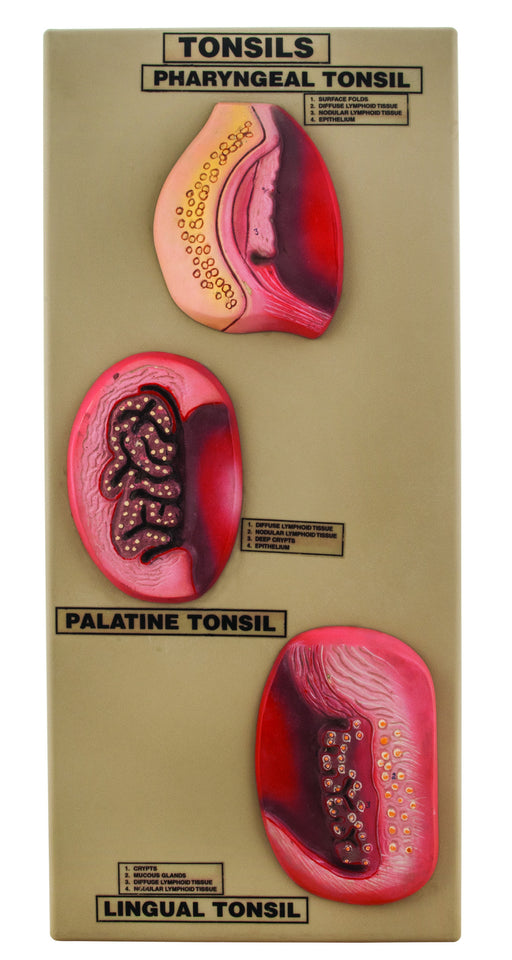

Model Tonsils

Set of 3 models showing an enlarged view of tonsils. Set of 3 models showing an enlarged view pharyngeal tonsils, palatine tonsils & lingual t...

View full detailsAM0258 -